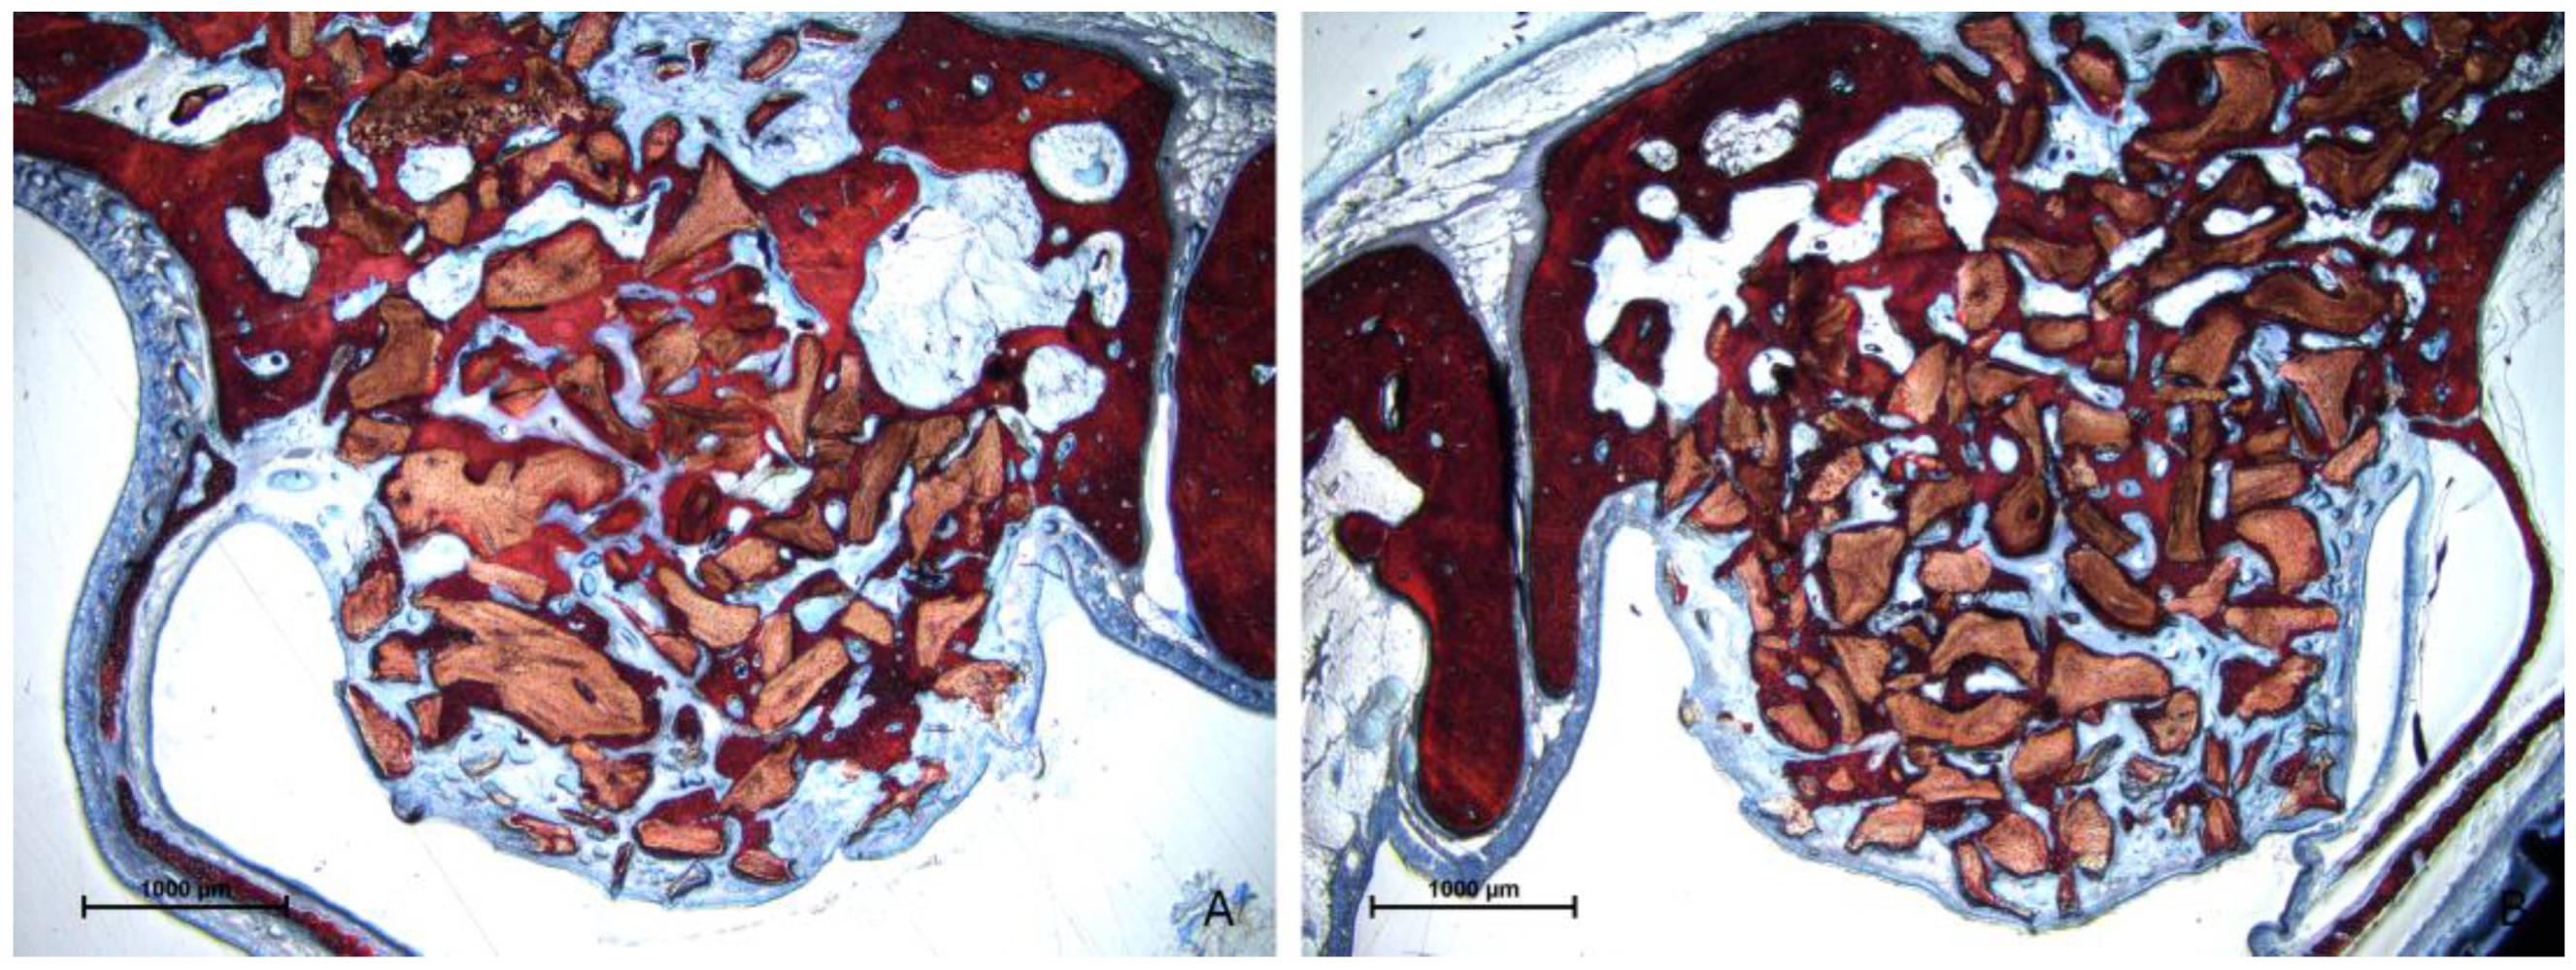

3.2. Descriptive Histological Evaluation